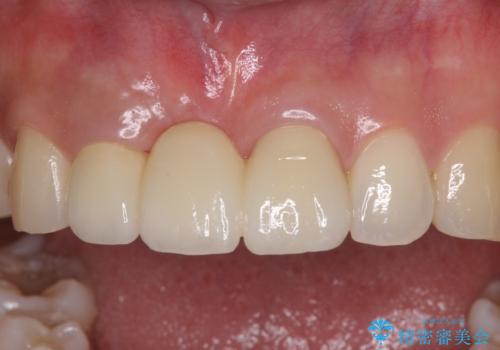

歯肉移植により歯肉ラインや歯の形態を整えることができ、ブリッジによる補綴としたことで舞えば全体の色調を整えることができました。